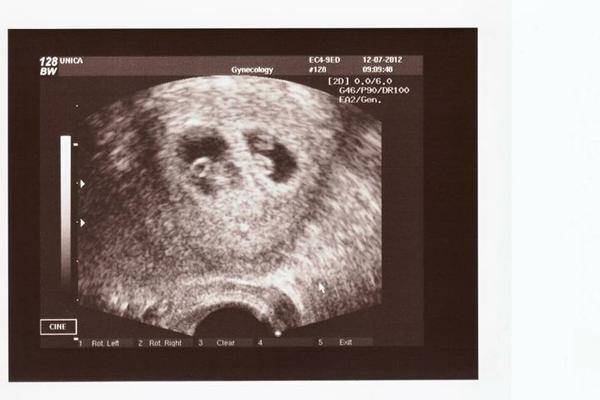

@zaneta2 (Unica Brno) 1. IVF červen/12 – 11.6. ET (2 E), 25.6. //, 12.7. UZV – čeká dvojčátka – gratulujeme!!! 😵 😵 😵